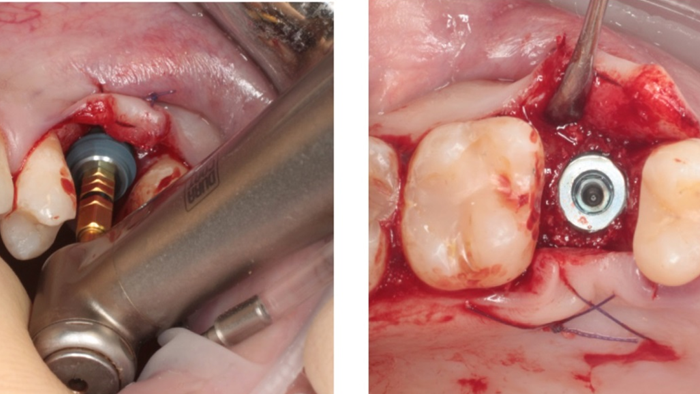

Clinical case: # 46 implant placement & GBR using i-Gen membrane for significant vertical resorption & mixed bone defect

- Courtesy of Dr. Iulian Filipov, Romania -

AnyRidge, mandibular posterior, i-Gen, resorption, bone defect, bone regeneration, space management, #46, GBR, Dr. Iulian Filipov

AnyRidge implant system, i-Gen

Thanks to MegaGen’s unique KnifeThread® and super self-tapping design, better initial stability can be attained in any compromised bone situation.

The design enables bone condensing, gentle ridge expansion, maximized compressive force resistance, and minimized shear force production.